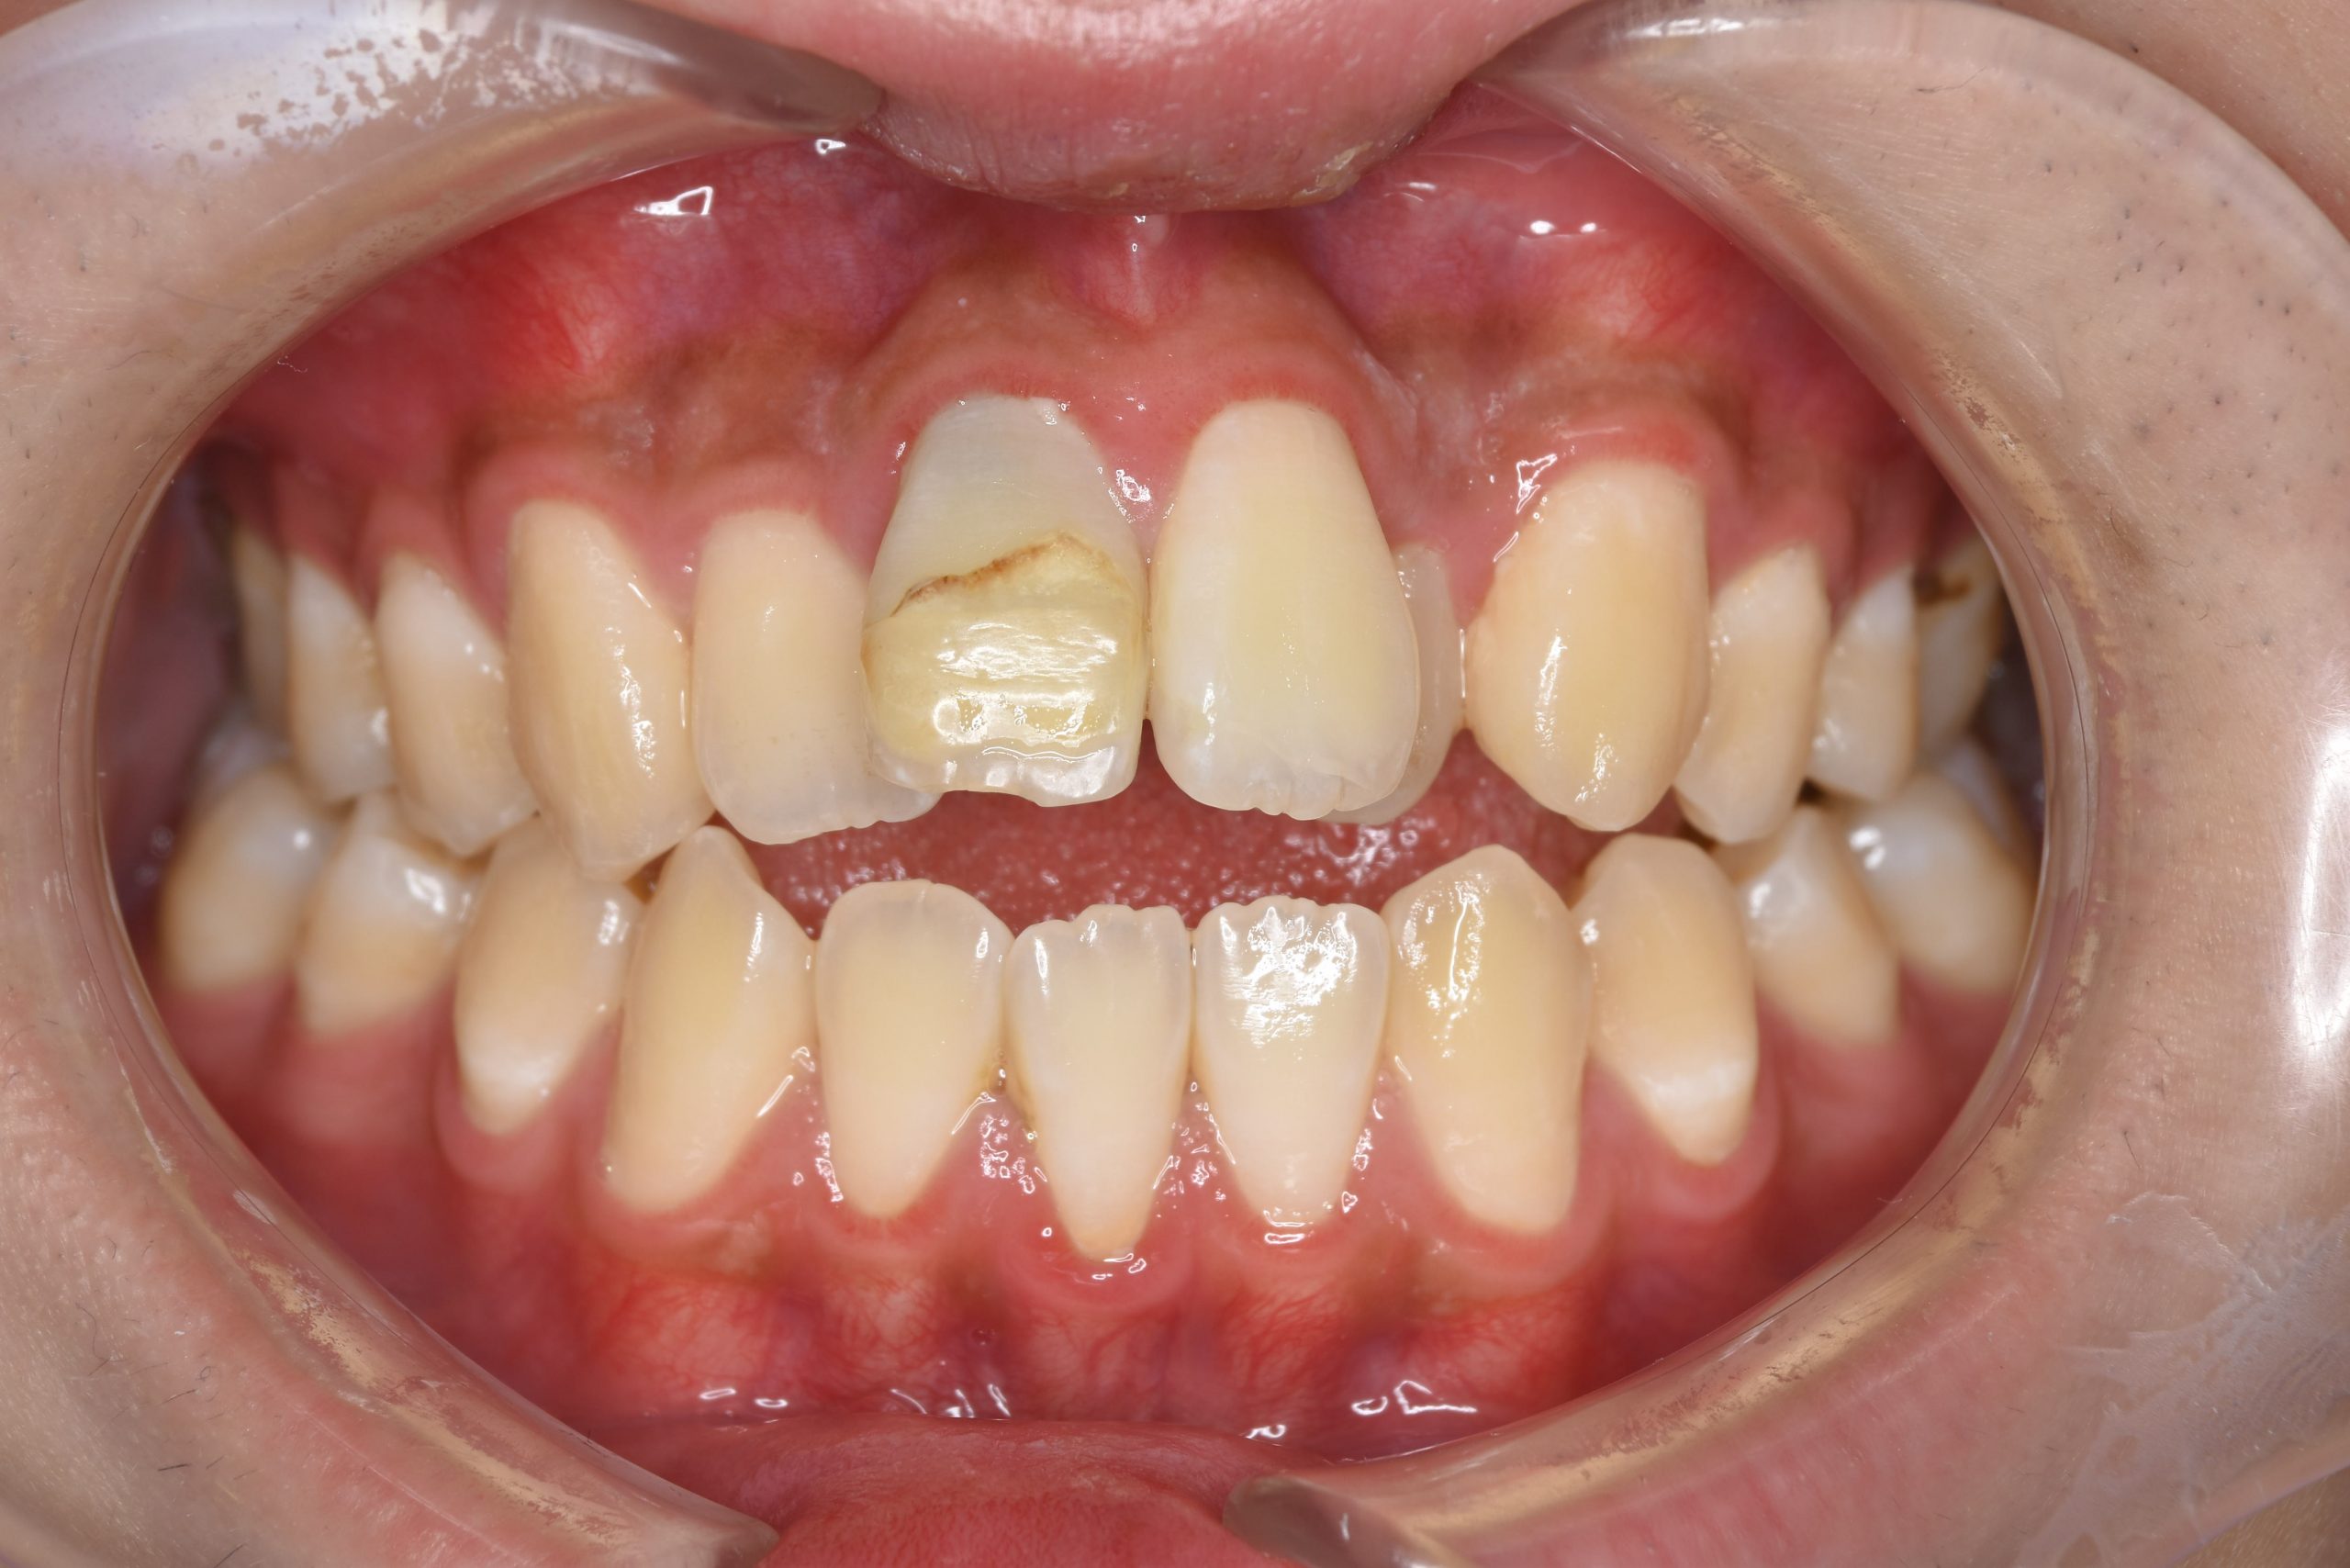

ビフォー

主訴 前歯が少し前に出ている|鼻づまり

施術内容 MSEと下顎リンガルアーチを用いて上下顎骨を拡大した。

その後をマルチブラケット装置を用いて非抜歯で歯牙を配列し、良好な咬合を獲得した。

治癒期間 1年6か月間